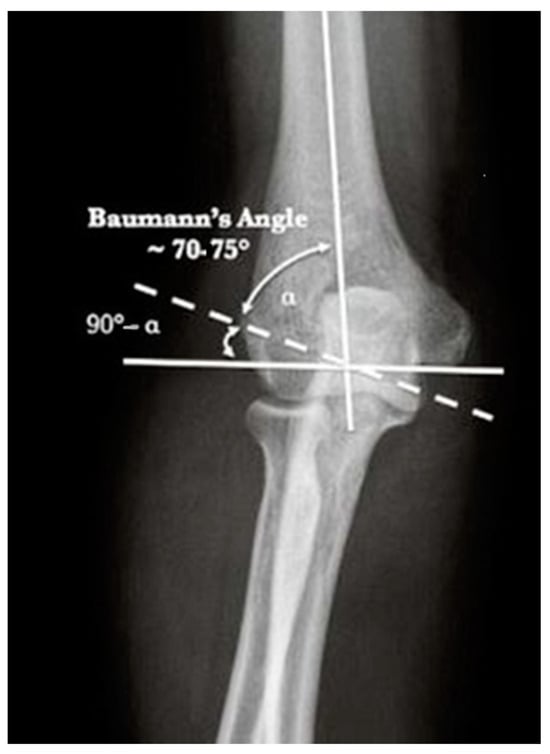

| Baumann Angle | 78.9° | 13.5 | 60.4–112° |

| Contralateral Baumann Angle | 79.1° | 12.7 | 63–118.8° |